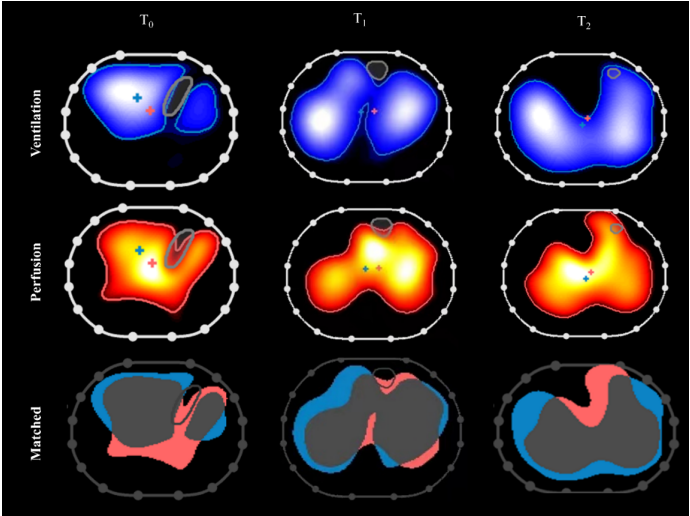

一项前瞻性观察性研究比较了D-二聚体与EIT评估肺栓塞的效能,结果发现,利用EIT测量V/Q比来诊断肺栓塞的灵敏度和特异度均高于D-二聚体。有研究发现EIT可对接受机械通气的ARDS患者的通气血流不匹配进行床旁评估。对不匹配单位的测量可以识别死亡风险较高的患者,并指导个性化治疗。笔者的一项研究通过EIT证实了吸入一氧化氮(NO)后机体的肺血流改变。通过EIT图像可以发现,吸入NO前,患者背侧有少许分流,吸入NO后,背侧分流减少,并且中央区域血流颜色变亮,说明血流更多。所以,我们可以用EIT监测患者的低氧原因以及评估治疗效果。

图片

图源:Am J Respir Crit Care Med, 2022, 205(9):1114.

笔者的另一项前瞻性生理性研究纳入10例接受俯卧位通气的ARDS患者,并在俯卧位开始时、俯卧位开始后3 h和俯卧位结束时进行了EIT评估。通过EIT发现,在俯卧位开始后3 h,背侧复张,匹配了背侧的分流,所以此时患者氧合就有改善。但随着俯卧位时间的延长,有更多的不张逐渐打开,在接近4区处通气和血流也有增加;在远期俯卧位时,氧合进一步改善。

图源:Crit Care, 2022 May 27;26(1):154.